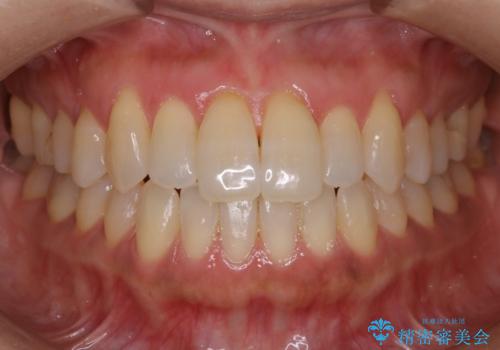

デコボコと変色した前歯 抜歯矯正と審美歯科治療